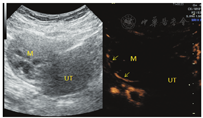

患者女,34岁,于顺产后43 d检查发现右侧卵巢囊实性肿块入院治疗。既往体健,生育史:孕4产2,曾流产2次。妇科查体:子宫正常大小,活动可,于右侧附件区可扪及一直径约5 cm肿块,活动可,界清,无明显压痛,左侧附件区未扪及明显肿块。辅助检查:CEA、CA199、CA125、AFP、卵巢癌相关抗原均为阴性。经阴道超声示:子宫体积正常(三径和约142 mm,宫颈厚28 mm,内膜厚约5.0 mm),宫壁未见明显肿块占位;右侧卵巢体积大、内可见一大小约49 mm×41 mm×39 mm的囊实性肿块,肿块边界清楚,形态规则,内部回声不均匀,可见多个囊性无回声区(较大者约13 mm×11 mm)(图1),能量多普勒示肿块内部及周边可见点条状血流信号(图2),脉冲多普勒(PW)示最高流速(Vmax)0.18 m/s,最低流速(Vmin)0.09 m/s,阻力指数(RI)0.50;子宫及左侧附件区未见明显异常回声。超声提示:①右侧卵巢内囊实性肿块;②子宫及左侧卵巢未见明显异常。进一步行超声造影成像示:增强早期时,右侧卵巢内肿块周边呈环状高增强,并早于子宫肌层增强(图3);内部实性部分呈不均匀等增强,并与子宫肌层同步增强;内部囊性部分无增强(图4)。造影剂消退时,肿块内部早于子宫肌层消退,而周边仍呈环状增强(图5),超声造影提示右卵巢肿块血供较丰富,表现"快进快退"。磁共振增强扫描提示:子宫右上方占位,考虑来源右卵巢性索间质肿瘤-颗粒细胞瘤可能,其他待排。术前拟诊"盆腔肿块性质待查",予行腹腔镜下右侧附件切除术,术中所见:右侧卵巢内见一肿瘤,直径约5 cm,呈囊实性,表面包膜完整,右侧输卵管攀附其上,外观正常;子宫正常大小,左侧卵巢及输卵管外观正常。术后病理镜下见肿瘤细胞弥漫性增生,呈片状、条索状,灶性腺样结构,部分区域可见大小不等的囊腔,核大小较一致,圆形或椭圆形,核仁可见,核分裂象约1~2个/10HPF,间质纤维组织及厚壁血管增生,黏液样变、灶性出血。免疫组化结果显示:Vimentin(+),CD10(+),ER(-),PR(-),CD34(血管+),EMA(-),P53(散在弱+),Ki67(灶性15%+)(图6)。结合免疫组化考虑卵巢性索-间质肿瘤,倾向卵巢间质瘤,送至复旦大学妇产医院会诊,诊断为右侧卵巢微囊性间质瘤。

卵巢MCST形态学表现上有完整的包膜,且实性肿块内部有特征性的微囊结构,这些在二维超声图像上有相应的表现,如本例患者卵巢MCST经阴道超声表现为卵巢内囊实性肿块,肿块边缘可见少量正常卵巢组织并与卵巢界线清楚,肿块边界清楚,形态规则,中央部可见多个规则的囊性无回声区(长径约10 mm)、透声好。彩色血流示肿块周边可见半环形血流信号,内部可见少许点状血流信号显示,频谱多谱勒显示为中等阻力。超声造影增强早期表现为包膜最先呈环状高增强(始增时间早于宫体),内部与宫体同步等增强,并由周围向中心增强,消退期表现为内部早于子宫肌层消退,而包膜仍呈环状持续高增强。